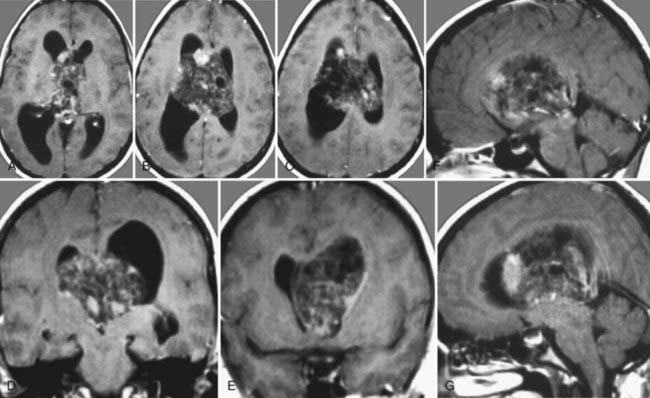

图138-7:一位有颅内压升高症状的26岁女性的术前轴向(A-C)、冠状面(D和E)和矢状面(F和G)磁共振图像。肿瘤(一个中枢神经细胞瘤)通过大脑半球间经胼胝体入路被完全切除。术后,缄默症被观察了几天,但在术后一周内完全消失。此后没有出现神经或认知缺陷。病人现在已经被连续监测了12年多,并且表现出了平安无事的过程、没有复发迹象。术者为巴特朗菲教授

案例报道原图